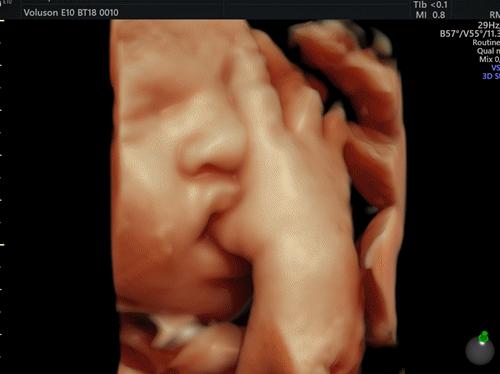

双顶径也叫“头部大横径”(BPD),指的是胎宝头部左右两侧之间最宽部位的长度。

“头围”指是从胎宝的鼻根到后脑的枕骨隆突处绕一周的长度,通常情况下双顶径和头围的值成正比。

双顶径数据比较重要的原因是,它可以判断出胎儿头部是否对称。简单来讲,数值越大代表胎儿头越大,不同孕周的双顶径有正常范围值,准妈妈可对照表格参考。